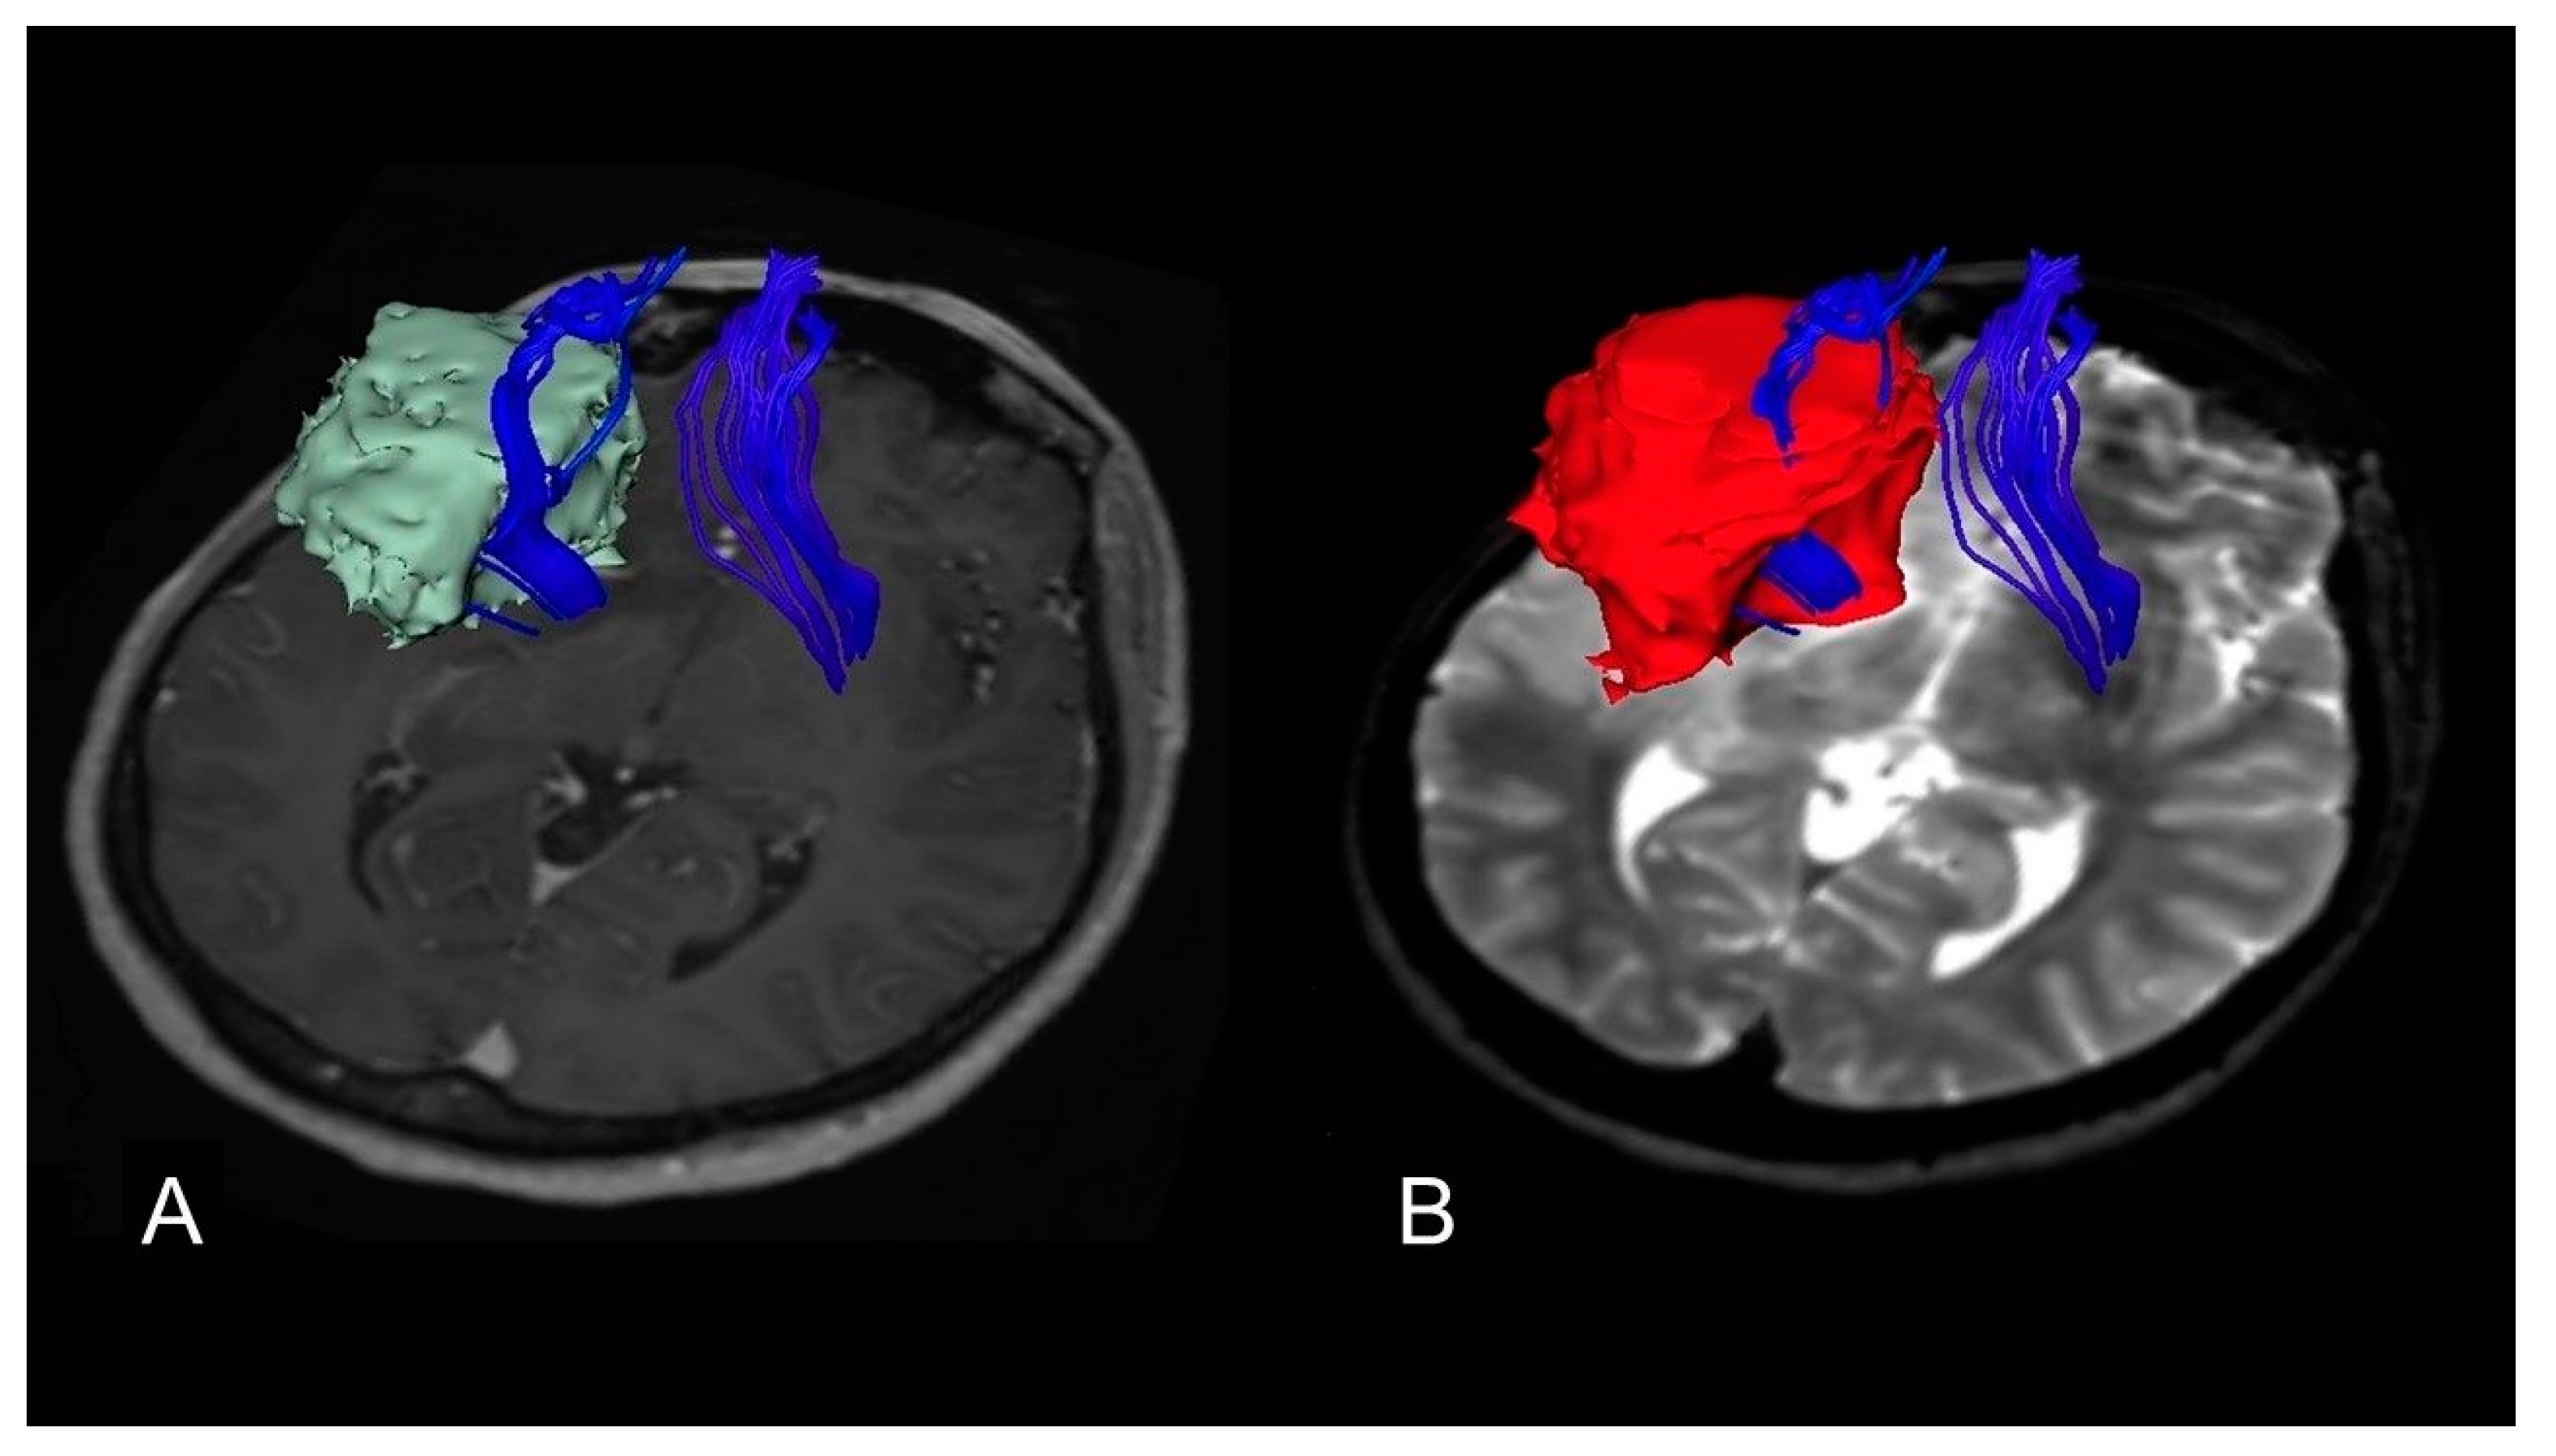

4.3. Volumetric Analysis